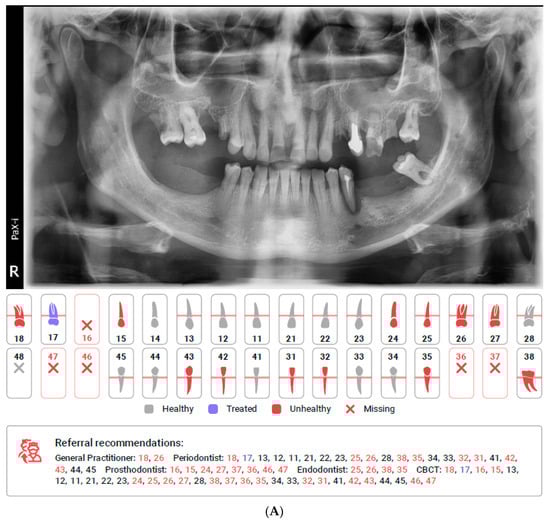

Figure 1.

(A). First page of the DC report including simple diagram of teeth with a legend of findings and referral recommendations pointing specific specialists for specific teeth. (B). One of the following pages of the DC report including specific teeth captions and description with percent of accuracy.